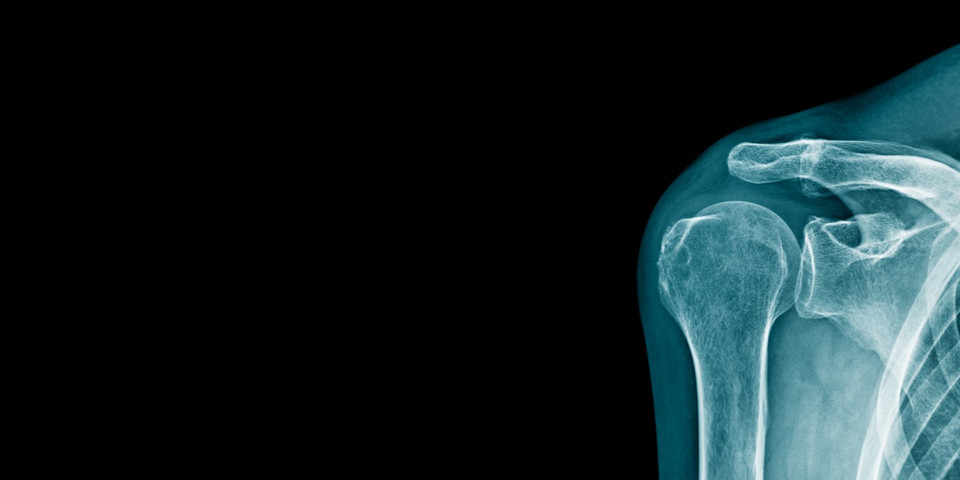

Learn about the causes of and treatments for shoulder pain.

The shoulder is a highly complex joint which allows for a large range in movement. But also because of its complexity there are numerous ways in which the joint can be affected and injured. Injuries to the shoulder most often affect muscles, tendons, or ligaments rather than bones. Common injuries to the shoulder include strains, sprains, and tears which can occur in a number of different variations - each affecting the shoulder differently.